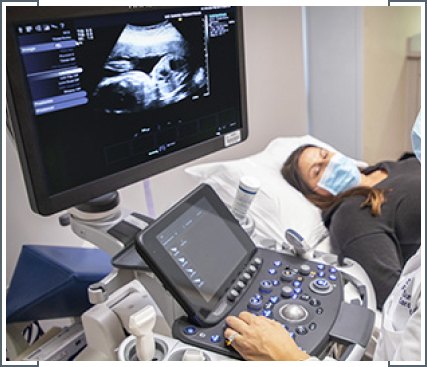

An anomaly scan or a mid-pregnancy ultrasound scan is a detailed examination performed around 18-22 weeks of pregnancy. Its primary purpose is to assess the baby’s growth and development, as well as to detect any structural abnormalities. During the scan, a trained sonographer examines various aspects, such as the baby’s head, brain, spine, heart, kidneys, limbs and umbilical cord. They also check the placenta and amniotic fluid levels. The scan provides crucial information to parents and doctors, helping to ensure the baby’s health and well-being throughout pregnancy and into birth, guiding any necessary medical interventions or preparations.

A growth scan with Doppler assessment is a specialized ultrasound procedure performed during pregnancy to evaluate the baby’s growth and assess blood flow within the umbilical cord and various fetal vessels. The scan measures the baby’s size, particularly focusing on head and abdominal circumference and femur length, to monitor growth patterns and detect any deviations from expected norms.

Doppler ultrasound is used to examine blood flow in the umbilical artery, middle cerebral artery and other vessels, providing insights into placental function and fetal well-being. This comprehensive assessment helps doctors monitor fetal development, identify potential issues early and make informed decisions regarding the management of pregnancy.